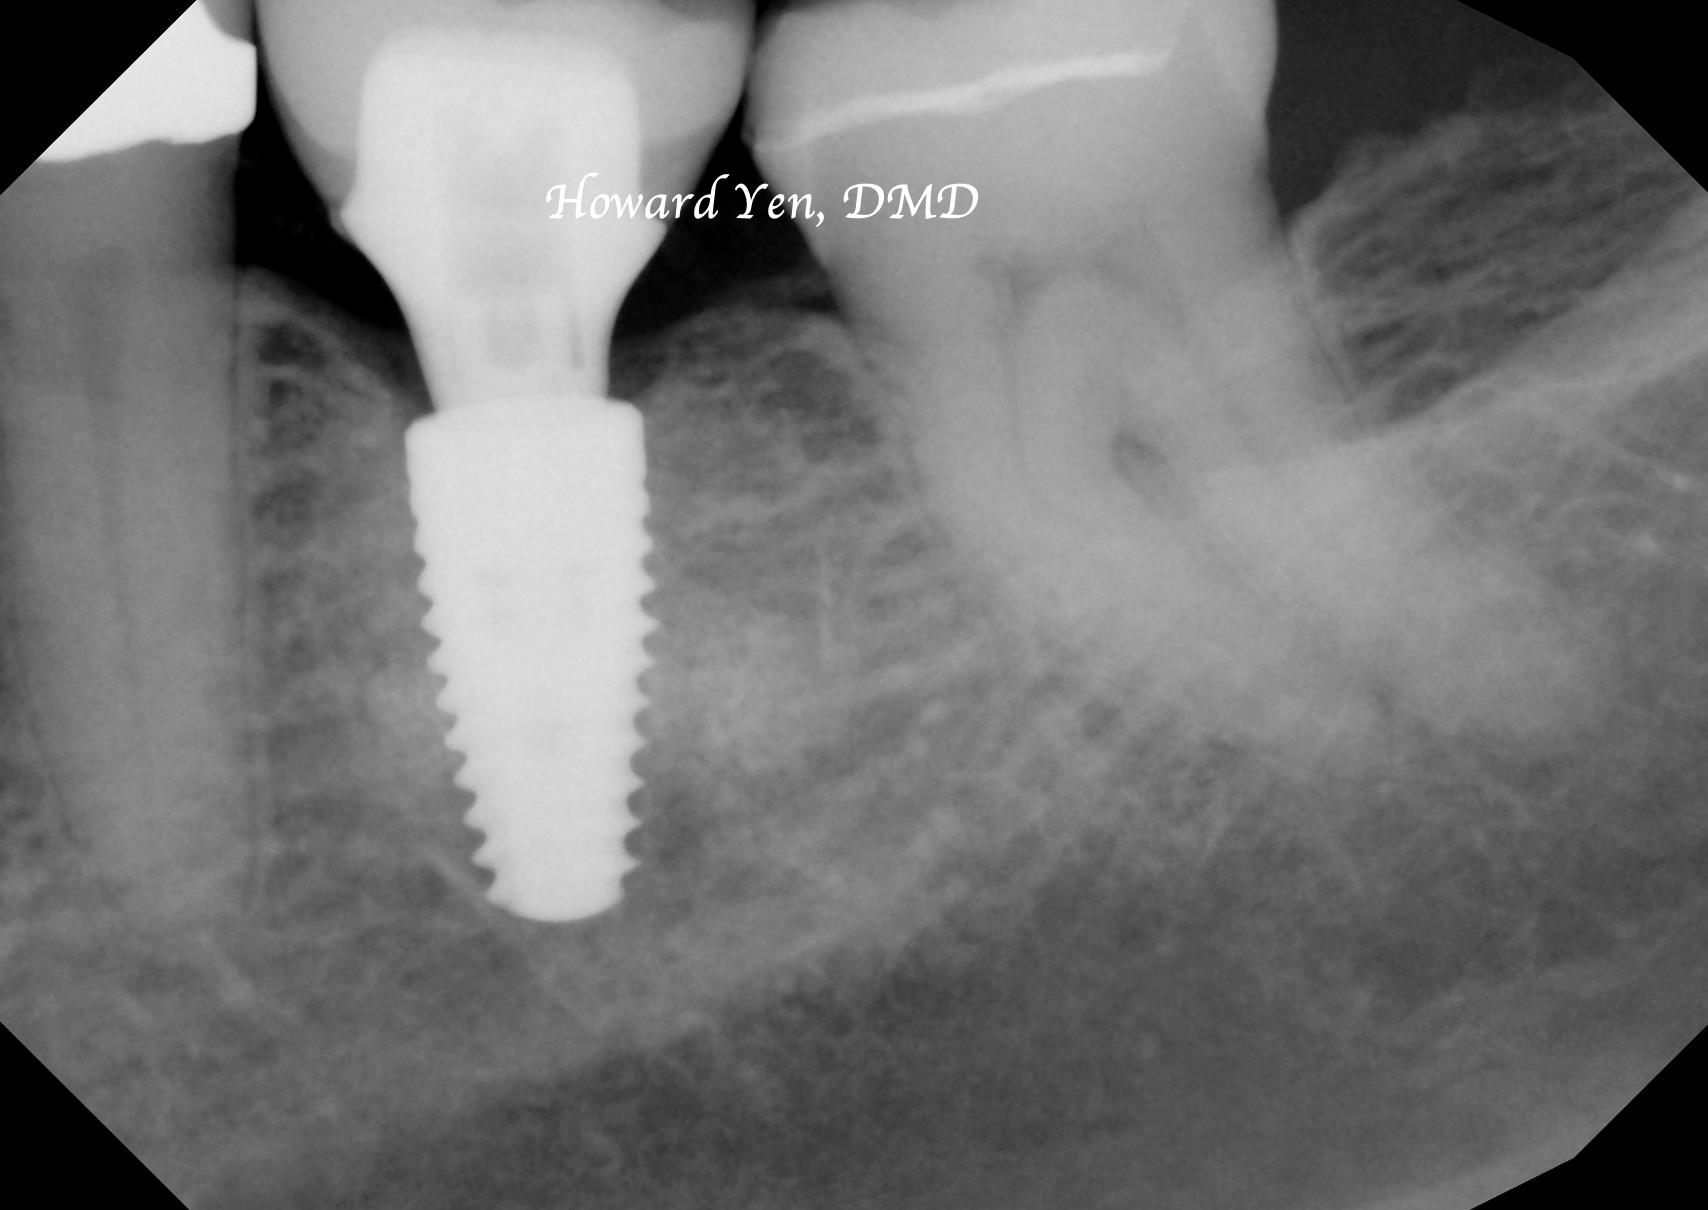

Once a natural tooth is removed from jaw bone, the jaw bone will undergo resorption (shrinkage) in volume. When there is a plan to replace the extracted tooth with dental implant, then there’s some treatment strategies to help reduce the rate of jaw bone shrinkage in order to provide adequate bone volume to receive dental implant. This procedure is often NOT necessary if there’s no plans to replace the tooth nor a strategic value (such as wisdom tooth extractions, the furthest molar in the mouth).